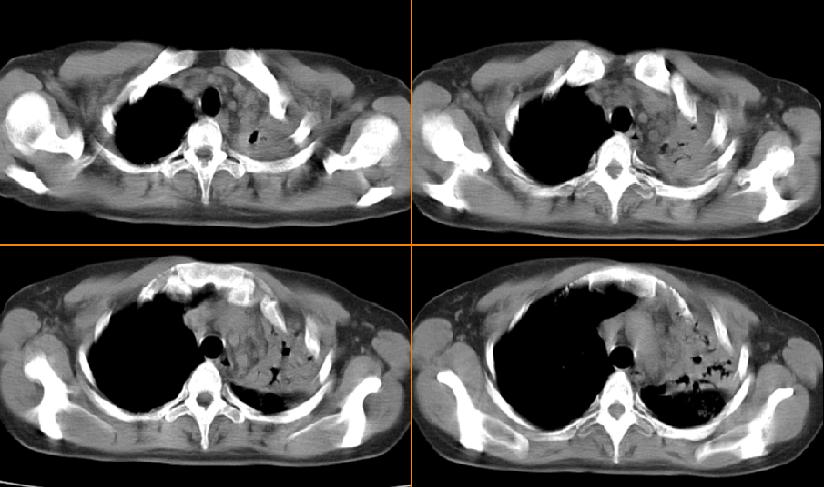

女,33岁,咳嗽5月。

左肺上叶前段致密,内见空气支气管征,相应部位胸膜增厚粘连,双肺上其他肺叶不同程度斑片状播散病灶,结合咳嗽5月的病史,考虑:双肺上叶继发性肺结核。

左肺上叶前段致密,内见空气支气管征,相应部位胸膜增厚粘连,双肺上其他肺叶不同程度斑片状播散病灶,结合咳嗽5月的病史,考虑:双肺上叶继发性肺结核伴左肺上叶肺含气不良。